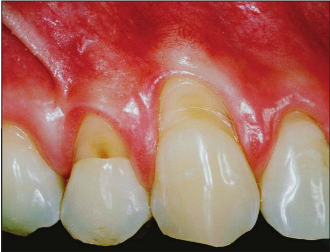

Cervical lesion treatment options of Connective Tissue Graft or Alloderm

Etiology of cervical lesions is multi-factorial.

| Before |